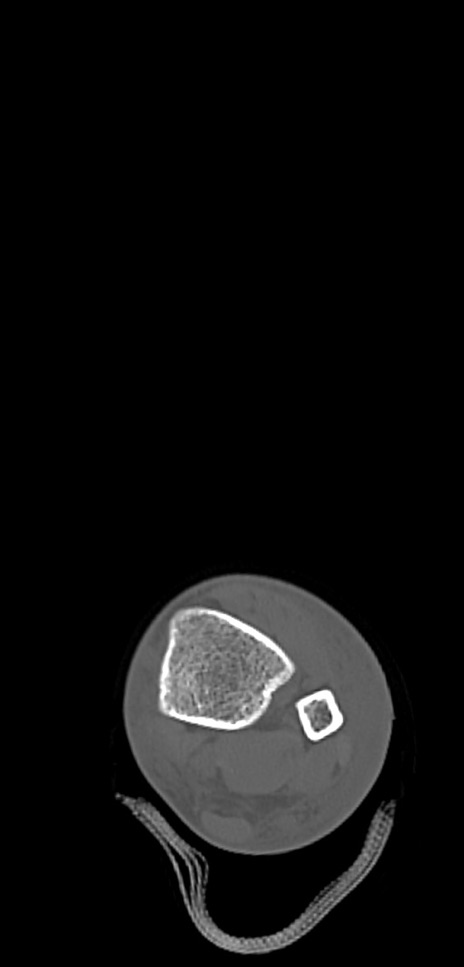

症例37 左足関節CT(横断像)

左足関節CT

冠状断像